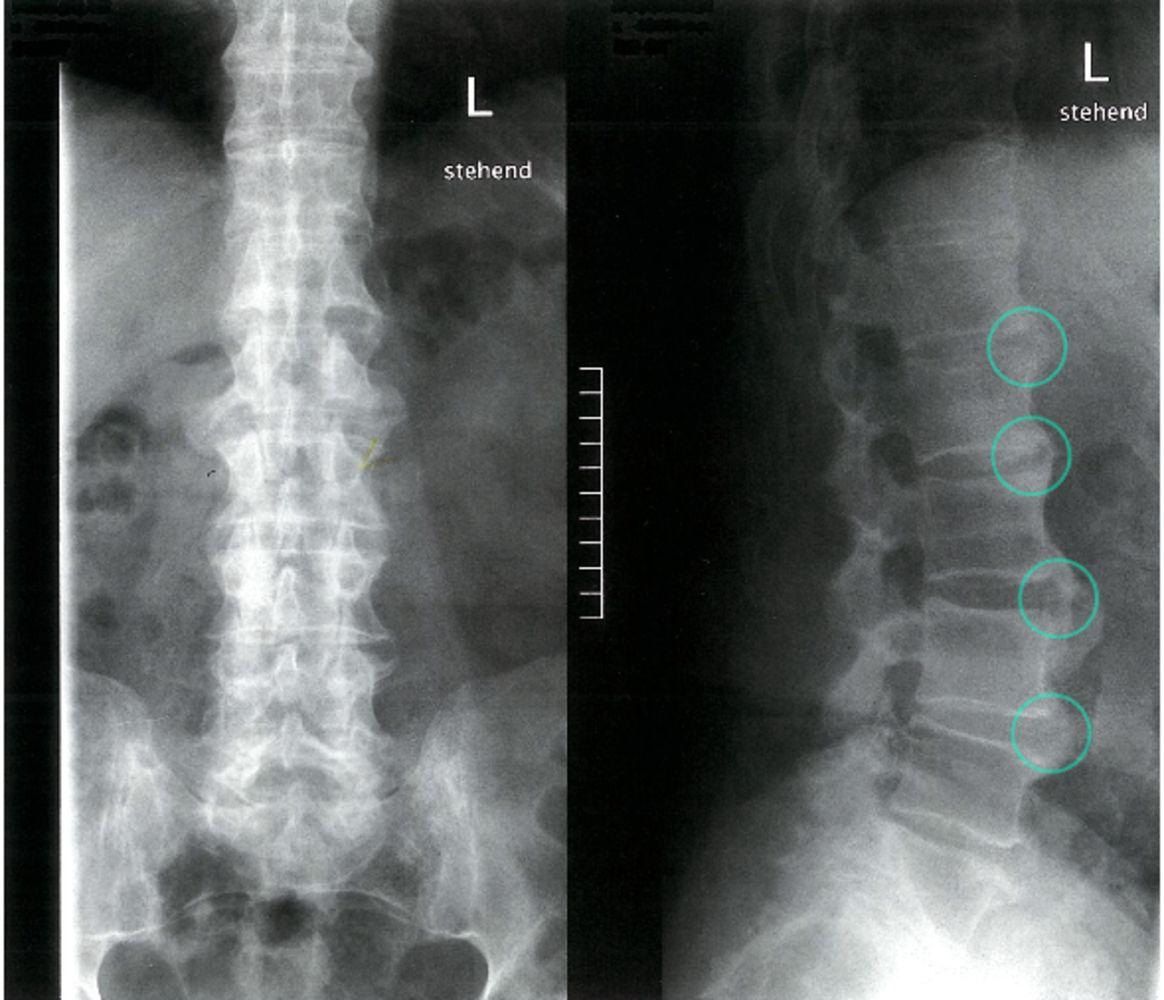

55歲黃先生,十多年前開始飽受下背痛之苦,尤其清晨睡醒時最嚴重,直至午後才緩解,經多年來四處求醫,診斷為強直性脊椎炎。幾個月前,疼痛從頸部延伸到下背部,伴隨雙側肩膀及左側髖部疼痛,醫生透過X光檢查發現,黃先生的雙側薦髂關節已完全融合,脊椎從頸椎下段到腰椎也有脊椎黏合情況。

X光檢查能看出薦髂關節和脊椎的變化,是診斷強直性脊椎炎最主要的方法。

陳昭宇解釋,診斷強直性脊椎炎通常依賴於臨床症狀、病史及影像學檢查。醫生會詳細詢問病人的症狀及家族史,並進行身體檢查。X光檢查能看出薦髂關節和脊椎的變化,是診斷強直性脊椎炎最主要的方法,但早期階段的疾病可能無法檢測出異常。磁振造影檢查(MRI)檢查則能更早期地檢測到關節及骨頭的炎症變化。此外,HLA-B27抗原的檢測也有助於診斷。